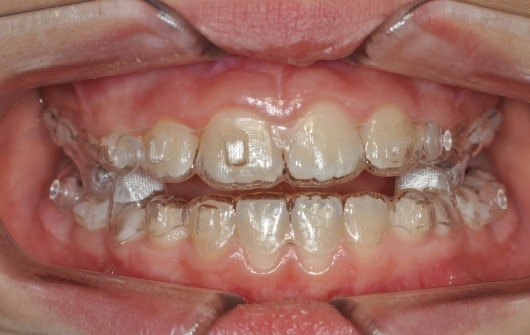

Malocclusion A6 Correction of Mandibular Retrusion in Growth phase patient | Skeletal Class II | Class II Division 1 malocclusion | Deep bite | Mixed dentition

Initial Photos and datas

Clinical examination and diagnosis

DENTAL:

• Molar and Canine class 2 on the right side – Molar and Canine clss 1 on the left side

• Upper diastema (11-21)

• Increased Overjet

• DeepBite

• Reduced Transversal Diameters

• Deviated Lower Midline 2 mm to the Right